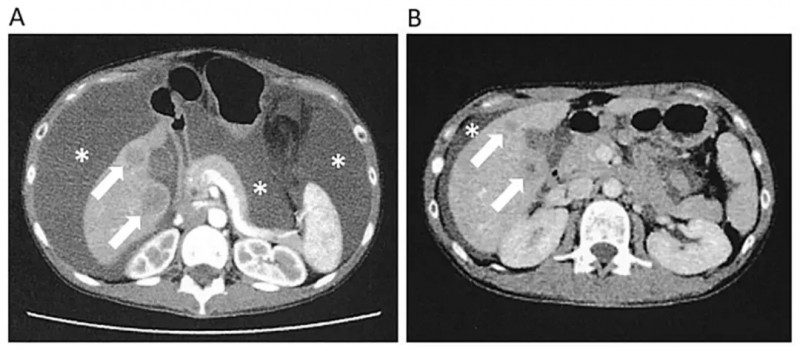

近期,一项针对不可切除PLC的临床研究(NCT03008343),共纳入40例原发性肝细胞癌(PLC)患者,随机分为单纯不可逆电穿孔(IRE)组(22例)、IRE联合同种异体NK细胞免疫治疗组(IRE-NK组,18例)。

结果显示:联合治疗组(IRE-NK组)的中位无进展生存期(PFS)和总生存期(OS)均显著优于单纯IRE组。具体表现为:IRE-NK组的中位PFS为15.1个月,而单纯IRE组仅为10.6个月(详见下图A)。两组1年OS率分别为77.8%、66.7%;中位OS分别为23.2个月、17.9个月(P=0.031,详见下图B),风险比(HR)为2.25(95%CI1.08–4.72)。

▲图源“Cardiovasc Intervent Radiol”,版权归原作者所有,如无意中侵犯了知识产权,请联系我们删除

综上,NK细胞联合疗法可显著降低循环肿瘤细胞(CTC)数量,提升患者免疫功能及Karnofsky评分,是一种前景广阔的新型联合疗法。